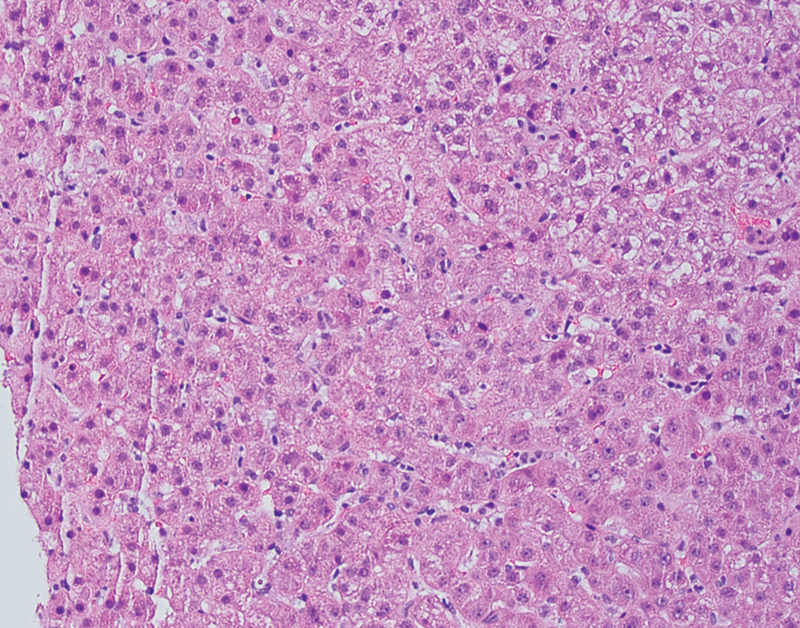

由严重急性呼吸系统综合征冠状病毒2引起的2019冠状病毒病(COVID-19)已引发全球健康危机。该病毒可引起不同程度的肝损伤,但其机制尚未阐明,特别是在妊娠期。我们报告了一名患有COVID-19的30岁病态肥胖女性,妊娠28周合并明显的转氨炎,肝酶水平峰值为501/ 1313(天冬氨酸转氨酶/丙氨酸转氨酶)。肝活检显示反应性改变,符合药物作用和轻度脂肪变性。在怀孕和非怀孕的COVID-19患者中都发现了明显的转氨炎。我们的病例显示了COVID-19患者肝损伤的多因素性质,包括轻度潜在肝脂肪变性,并可能伴有病毒增强药物作用。

Coronavirus disease 2019 (COVID-19), caused by severe acute respiratory syndrome coronavirus 2, has led to a global health crisis. The virus can cause varying severity of liver injury, but the mechanism has not yet been elucidated, especially in pregnancy. We present a morbidly obese 30-year-old woman with COVID-19 at 28 weeks' gestation complicated by significant transaminitis with peak liver enzymes levels of 501/1,313 (aspartate aminotransferase/alanine aminotransferase). Liver biopsy showed reactive changes consistent with medication effect and mild steatosis. Significant transaminitis has been found in both pregnant and nonpregnant patients with COVID-19. Our case demonstrates the multifactorial nature of liver injury in COVID-19 patients including mild underlying liver steatosis combined with possible viral potentiation of medication effect.